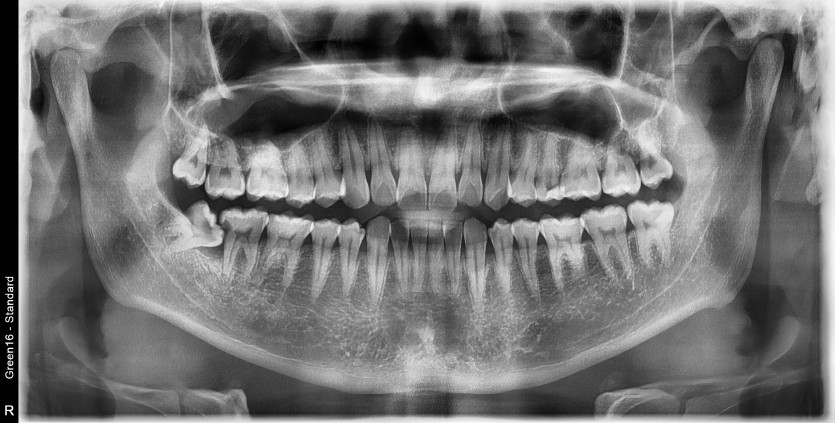

#48 사랑니 발치

구강 외과 전문의가 당일 발치했습니다.